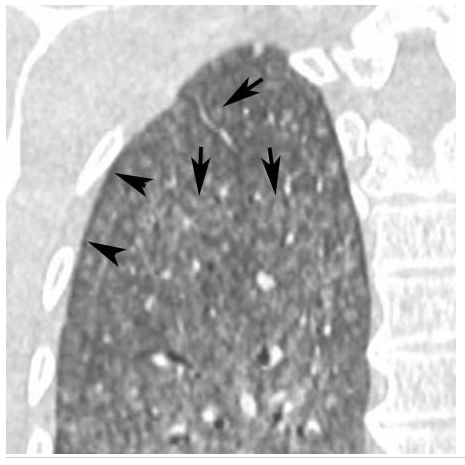

Lésions élémentaires ?

Dg ?

Pneumopathie d’hypersensibilité.

Agrandissement sur le sommet droit d’une coupe frontale. Micronodules à limites floues (flèches) de distribution diffuse dans les deux poumons. Leur topographie centrolobulaire est attestée par l’absence de micronodules sous-pleuraux (têtes de flèches).